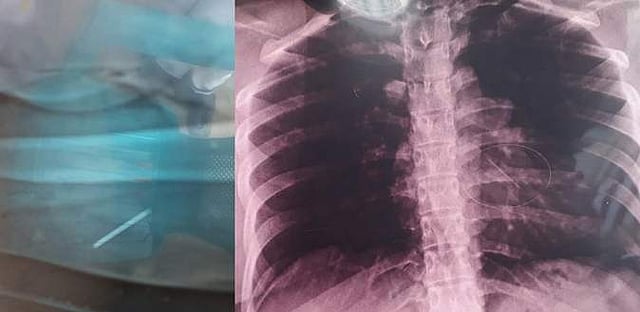

கையினுள் ஊசி இருப்பது தெரியாமல் வீடு திரும்பிய சசிகலாவுக்கு நாளடைவில் கையில் கடும் வலி ஏற்பட்டிருக்கிறது. மீண்டும் அவர் கும்பகோணம் அரசு மருத்துவமனைக்கே சிகிச்சைக்கு வர, அப்போது அவருக்கு எக்ஸ்ரே எடுக்கப்பட்டது. அந்த எக்ஸ்ரேவில் சசிகலாவின் கையினுள் உடைந்த ஊசி இருப்பது தெரிய வந்தது. அதைக் கண்டதும் சசிகலாவும், அவரது கணவர் வடிவேலுவும் கடும் அதிர்ச்சி அடைந்தனர்.

இந்நிலையில் தற்போது கர்ப்பிணியாக உள்ள சசிகலாவுக்கு சமீபத்தில் நெஞ்சில் கடுமையான வலி ஏற்படவே, அருகில் உள்ள தனியார் மருத்துவமனையில் சிகிச்சைக்காகக் காட்டியுள்ளனர். அப்போது மீண்டும் அவருக்கு எக்ஸ்ரே எடுக்கப்பட, அந்த எக்ஸ்ரேவில் சசிகலாவின் கையில் இருந்து அகற்றப்பட்டதாகக் கூறப்பட்ட உடைந்த ஊசி தற்போது அவரது நெஞ்சுப் பகுதியில் இருப்பது தெரிய வந்திருக்கிறது.